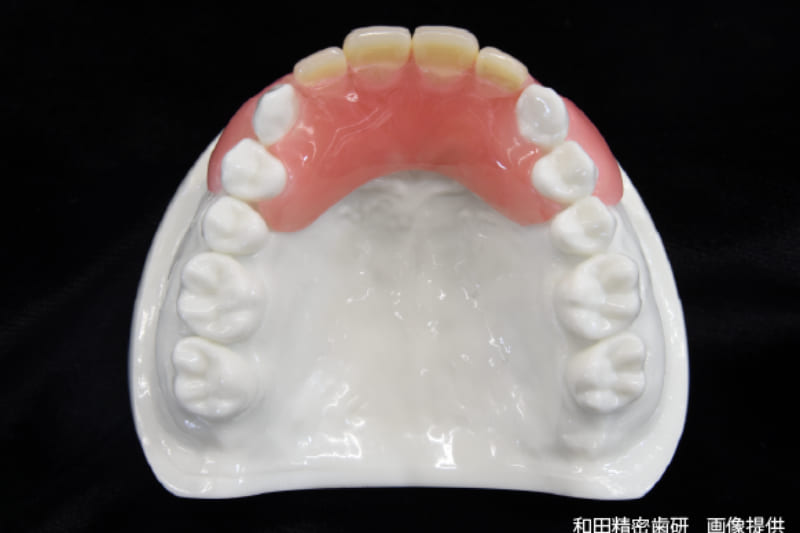

義歯(入れ歯)

義歯(入れ歯)は失った歯を補う方法として代表的な存在です。当院では保険診療と自費診療の両方の入れ歯を扱っていますが、基本的に保険診療の入れ歯をご提案しています。とはいえ、保険診療の入れ歯を使ったうえで、「もっと噛みやすい入れ歯が欲しい」、「審美性が高い入れ歯を作りたい」というご要望に対しては自費診療の入れ歯を作製いたします。

いずれの場合もメリット・デメリットを丁寧に説明しますので、わからないことがあれば何でもお尋ねください。

当院で取り扱いのある

入れ歯の種類の例